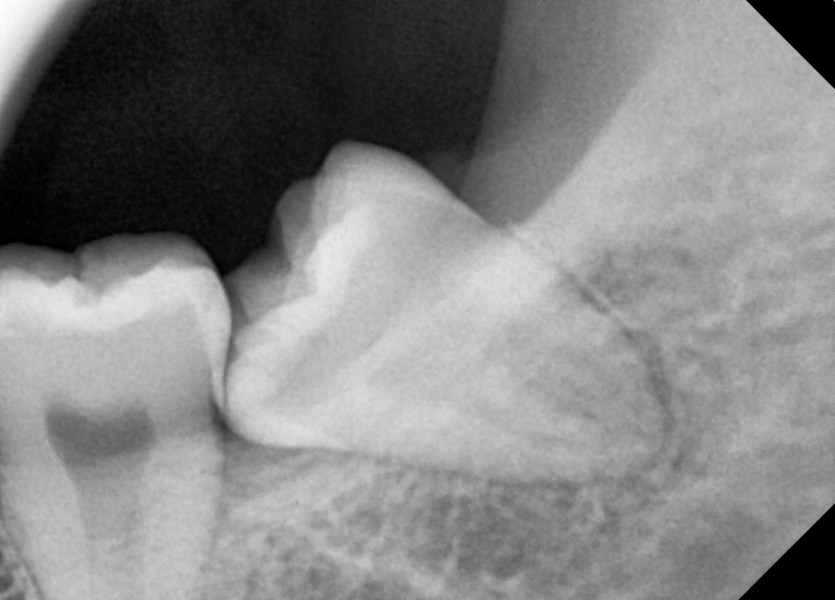

#38 사랑니 발치

구강 외과 전문의가 당일 발치했습니다.